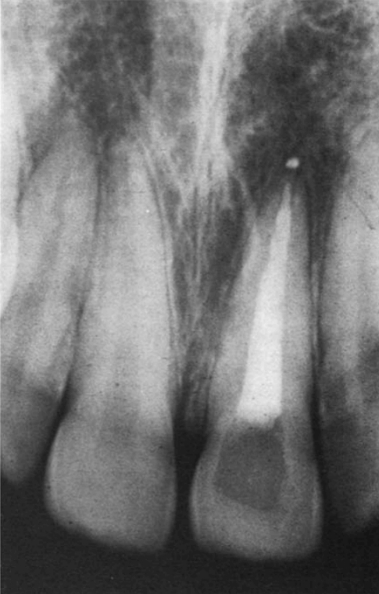

В 1971 году, через 3,5 года после процедуры отбеливания, пациент вернулся с жалобами на периодически возникающий отек десны между правыми центральным и боковыми резцами верхней челюсти. На слизистой оболочке с щечной стороны на несколько миллиметров ниже свободного края десны между двумя зубами имелся свищевой ход. Рентгенограмма (рис. 7) показала обширную наружную резорбцию в цервикальной области как с мезиальной, так и с дистальной поверхности корня.

Рис. 7 - Клинический случай 3. Рентгенограмма в 1971 году, показывает обширную наружную резорбцию в цервикальной области как на мезиальной, так и на язычной поверхности корня.